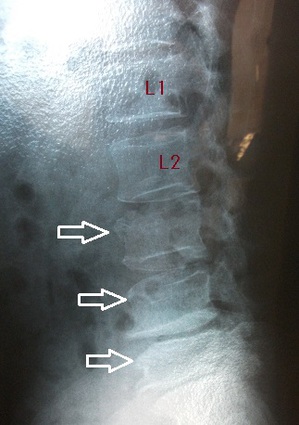

腰部レントゲン側面像 腰部レントゲン正面像

すぐに同僚が近くの病院へ連れて行ってくれました。レントゲン撮影の結果、第3、4、5腰椎の圧迫(多発)骨折が

判明致しました。多発骨折とは、同時に2つ以上の骨が骨折することを言います。(左右上画像の矢印)

左右上画像の第1腰椎(L1),第2腰椎(L2)と比較すると、椎体の前面がくさび形に、あるいは椎体全体が圧潰されて

変形してしまいます。